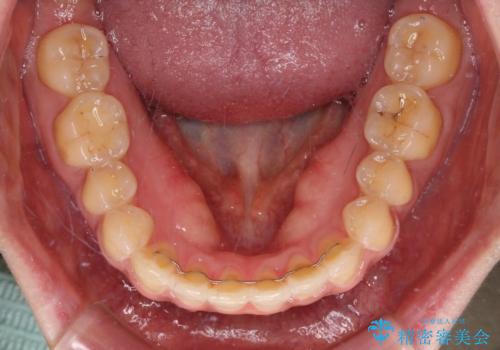

舌のトレーニングをしっかりと行っていただき、上下前歯をしっかりと接触させることができました。

咬合力が強いため、治療途中に奥歯が咬み合わない期間が続きましたが、上下の奥歯でゴムかけを行っていただき、違和感なく咬み合うように仕上げることができました。